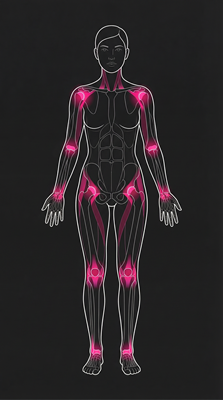

Powerful Antioxidant & Anti-inflammatory Effects

Polyphenols, phenolics, flavonoids, and tocopherols neutralize free radicals, reduce oxidative stress, and provide anti-aging benefits. Prevents cellular damage linked to chronic diseases.

Cardiovascular Support

Unsaturated fatty acids (especially linoleic acid) may help lower cholesterol levels and reduce risk of heart disease.

Immune System Support

Polysaccharides help regulate and strengthen immunity against infections and disease.

Digestive Health

High dietary fiber (7–15g/100g) promotes regular bowel movements and prebiotic effects.

Bone Health

Ergosterol (vitamin D precursor) supports calcium absorption and bone mineralization.